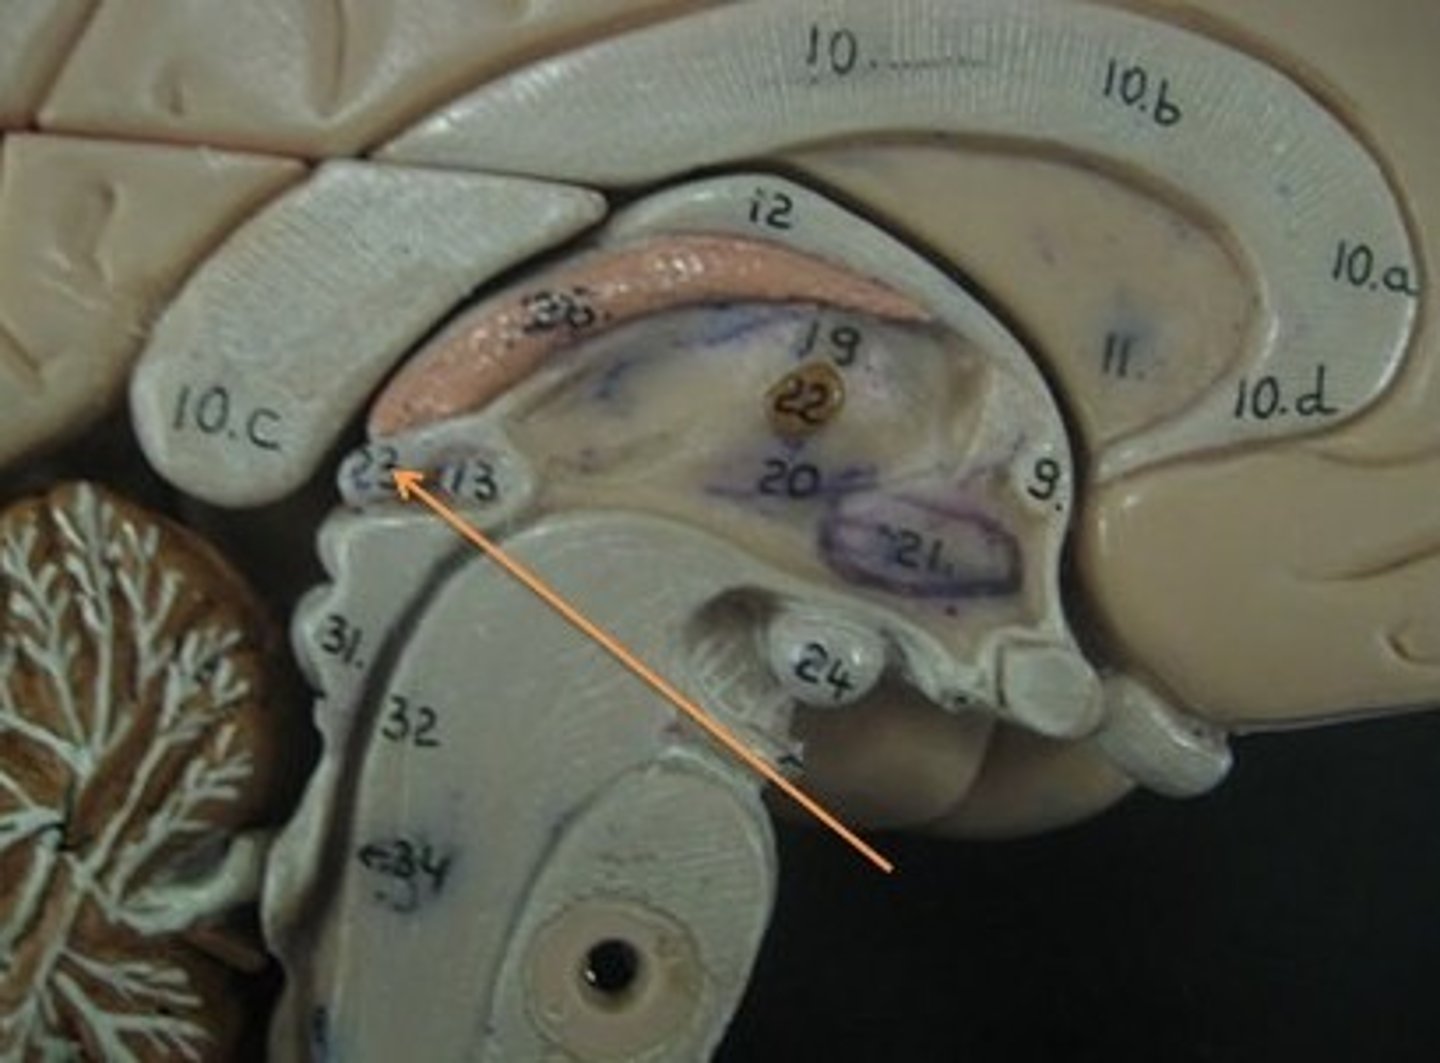

lateral ventricles

third ventricle

fourth ventricle

interventricular foramen

connects lateral ventricles to third ventricle

cerebral aqueduct

connects the third and fourth ventricles

choroid plexus

on the floor of all the ventricles, produces CSF

arachnoid villi

diencephalon

thalamus and hypothalamus

thalamus

relay station for all somatosensory information

intermediate mass

connection between the two thalami across the third ventricle, dumbbell shape

hypothalamus

brain region (many nuclei) in charge of maintaining homeostasis

pituitary gland

produces hormones

mammillary bodies

olfactory relay stations

epithalamus

region above midbrain that contains pineal gland

pineal gland

regulates sleep-wake cycles, secretes melatonin

basal nuclei

internal masses of gray matter, smooth out motor movement

fornix

band under septum pellucidum